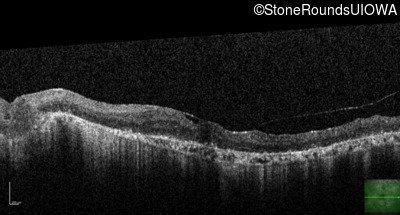

Type 1 Usher Syndrome (IB1a)

Age at visit: 62 years

This 62 year old man has had profound hearing loss since birth and has communicated using sign language for his entire life. He first noticed a problem with his vision at about age 11 when he noticed night blindness and began to trip over objects that he should have seen.